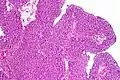

| Histopathology of transitional carcinoma of the urinary bladder. Transurethral biopsy. Hematoxylin and eosin stain. | |